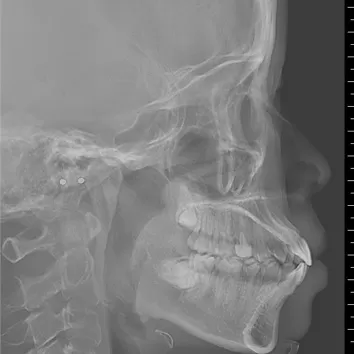

X-rays before treatment

[Panoramic Radiography/Lateral Cephalogram]